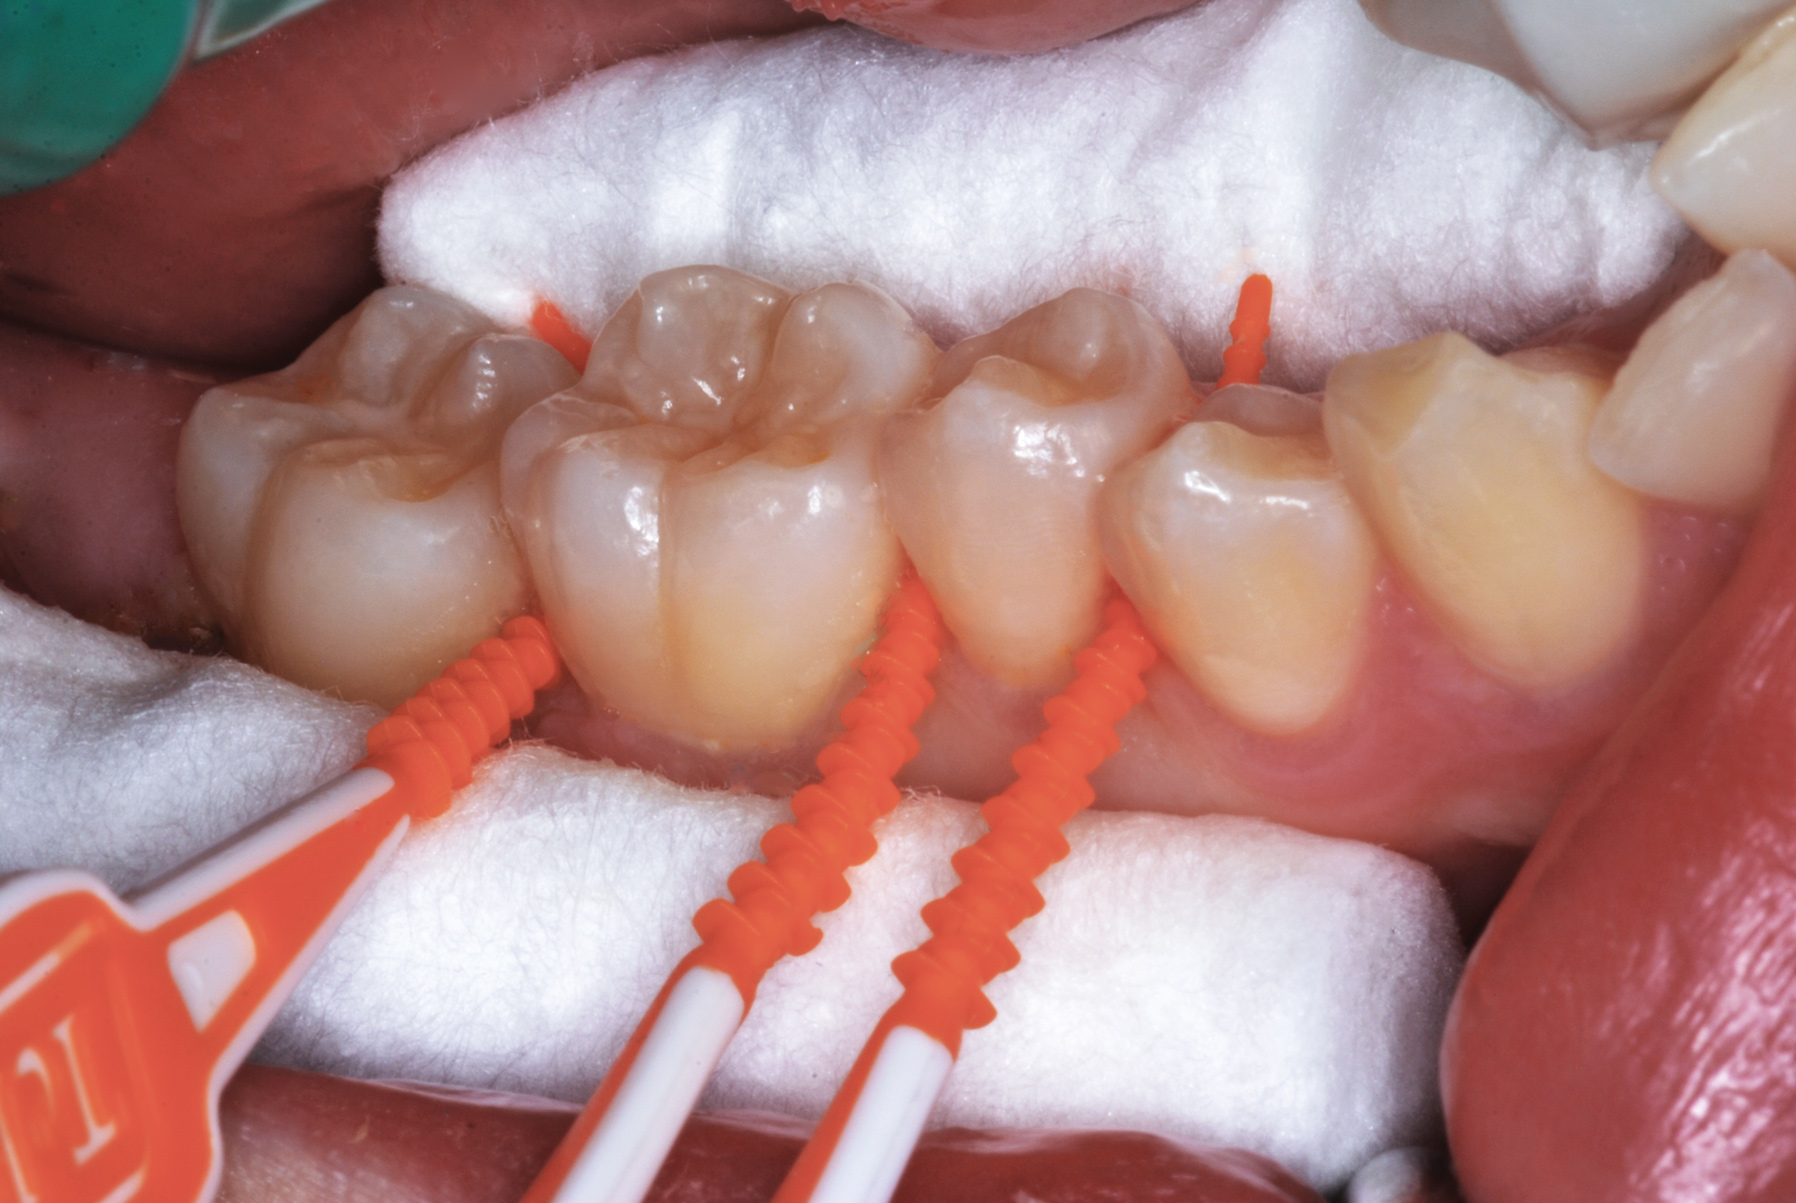

The authors' protocol for insertion of SDF-coated soft dental picks involves isolating the teeth with cotton rolls or other means, flossing the interproximal site to clear food debris and dental plaque, and then inserting a SDF-coated pick (Figure 1 and Figure 2) to saturate the contacting surfaces of the teeth with the fluid. This treatment is painless and requires no anesthetic. The pick should remain in place for at least 60 seconds and can be gently pulled in and out to agitate the fluid for enhanced surface coverage by capillary action. Additional SDF can be wiped on, using a small applicator, above the contact and in the buccal and lingual sluiceways. Excess fluid and any blood elicited may be blotted with a cotton swab. An additional 60-second insertion may be applied in the same way if there is radiographic evidence of a deeper decalcification or caries lesion. With the pick still in place, 5% (or 2.5%) fluoride varnish is painted over the treatment area, and the pick is then withdrawn.

Interproximal insertion of SDF is demonstrated in different patients in Figure 3 through Figure 11. Various diameters and brands of soft dental picks may be used depending on the closeness of the proximal surfaces and ease of insertion; for example, some picks are designed for use in wider spaces between teeth. This protocol also offers versatility. Figure 3, for example, shows the simultaneous use of three thin soft dental picks to saturate proximal surfaces with SDF in a teenaged patient; the treated regions were subsequently covered with fluoride varnish (Figure 4). This patient was initially treated in April 2019 (Figure 5), with an identical re-application 3 months later. As shown in Figure 6, the December 2019 bitewing film revealed good results with the possible exception of the contact regions of the maxillary first and second molars. New SDF application was completed in the December appointment.

Fig 3. Three thin soft dental picks were used simultaneously for SDF proximal surface saturations in a teenaged patient (Fig 3). After 60 seconds, the treated regions were covered with 5% fluoride varnish (Fig 4). A comparison can be seen of pre-SDF-treatment bitewing films (Fig 5) and 8-month post-SDF bitewing films (Fig 6) for the patient shown in Fig 3 and Fig 4. Radiolucencies were similar or improved, except for contact of maxillary first and second molars.

Figure 3

Fig 4. Three thin soft dental picks were used simultaneously for SDF proximal surface saturations in a teenaged patient (Fig 3). After 60 seconds, the treated regions were covered with 5% fluoride varnish (Fig 4). A comparison can be seen of pre-SDF-treatment bitewing films (Fig 5) and 8-month post-SDF bitewing films (Fig 6) for the patient shown in Fig 3 and Fig 4. Radiolucencies were similar or improved, except for contact of maxillary first and second molars.

Figure 4